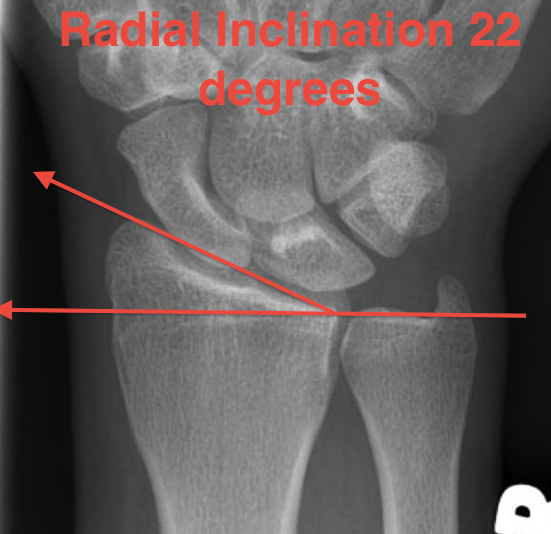

Distal Radius Angles

- radial inclination  22°

4.  Radial inclination < 15o